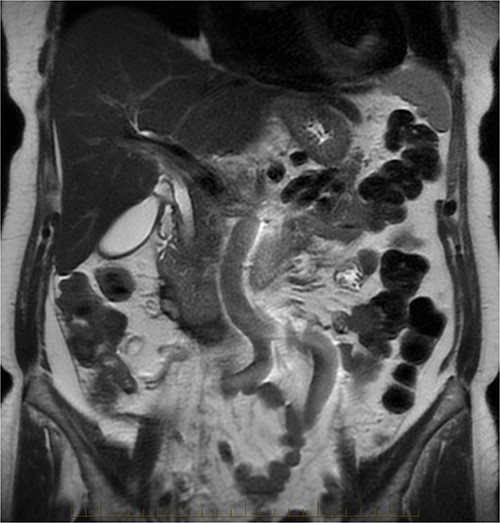

After further discussion with the reporting radiologist, a magnetic resonance imaging (MRI) was performed, which confirmed the presence of an acute periduodenal hematoma surrounding D2 and D3, lying in the retroperitoneal space, anterior to the right perirenal space. Etiology was uncertain. No abnormal enhancement within the bowel to suggest a bowel wall lesion or infiltrating mass (Figs 3 and 4).

MRI abdomen, axial view. T2 hypointense, T1 iso to hyperintense material surrounding D2/D3 without enhancement in keeping with hemorrhage. No vascular or bowel wall lesion identified.